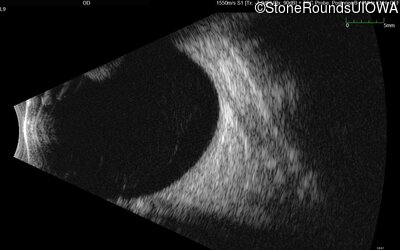

B-Scan Ultrasonography - Right - Light Perception

Exemplar